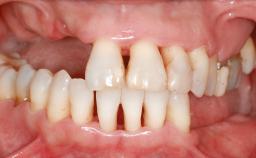

A 56-year-old woman presented for treatment with complete edentulism of the maxilla. She had been using a complete removable denture since she was relatively young (age 30). Her chief complaint at presentation was lack of retention of the upper denture and a desire for a better restoration in order to improve retention, function, and esthetics. An initial clinical examination showed that the anterior maxilla was moderately atrophic both horizontally and vertically, also revealing a vertical deficiency of the posterior alveolar process. The mandible included natural teeth from 45 to 35, with previous extrusion of the anterior teeth that was being orthodontically treated. Also, there were two external hexagon dental implants at sites 46 and 36 that had been inserted elsewhere at a previous point in time. As the conditions in the mandible were healthy, including the teeth and the two implants, the patient had no complaints there.